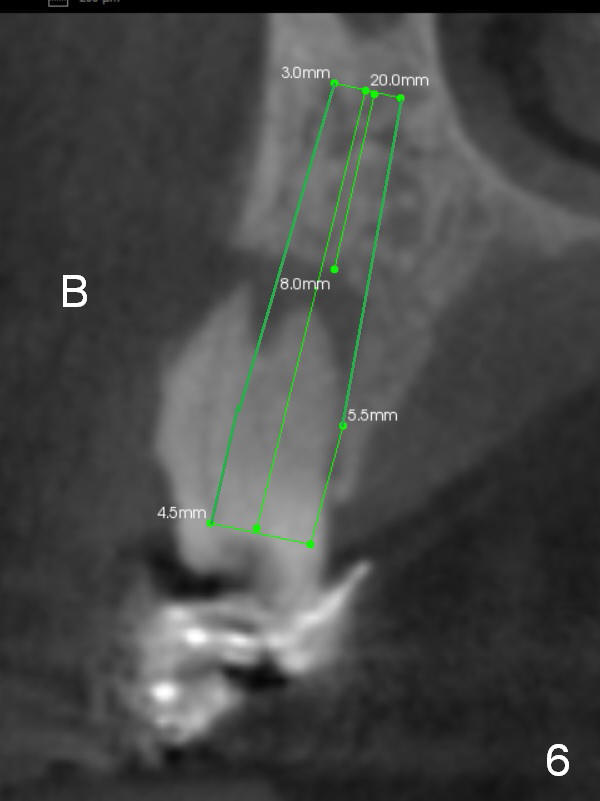

Fig.6,7 are coronal sections of the teeth #5 and 6, respectively. The buccal (B) plate is completely (Fig.6) or partially (Fig.7) lost. Osteotape is to be inserted between the buccal gingiva and the implant.

To avoid or reduce the chance of using an angled abutment at #6, the apical end of the implant should be placed as close to the buccal plate as possible (Fig.8 red arrow). Compare the angles at the implant crown (Fig.7,8). Initial osteotomy depth is 17 mm; insert parallel pins and take PA for checking trajectory (Fig.4). When fabricating provisional crowns, make sure that they are palatal to the lower counterparts (cross bite), both right and left.